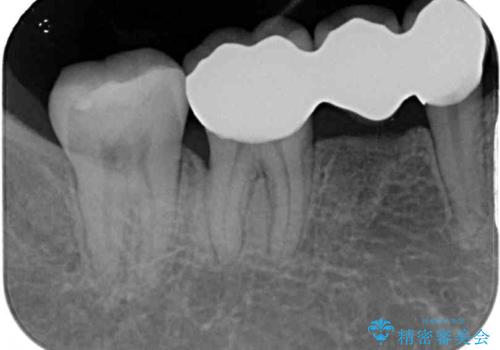

右下の欠損分は奥歯が倒れ込んでスペースがなくなっていたため、矯正治療により本来の位置に歯を移動させ、オールセラミックブリッジによる欠損補綴治療を行うこととしました。

右下は移動量が多いため、十分な移動が達成されない場合はワイヤー装置を使用する予定としておりましたが、しっかりとマウスピースを装着してくださったため、前歯とともに十分に歯を動かすことができました。